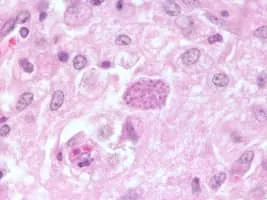

Neospora caninum photograph

Neospora Caninum

Neospora caninum is a coccidian parasite that was identified as a species in 1988. Prior to this, it was misclassified as Toxoplasma gondii due to structural similarities. The genome sequence of Neospora caninum has been determined by the Wellcome Trust Sanger Institute and the University of Liverpool.